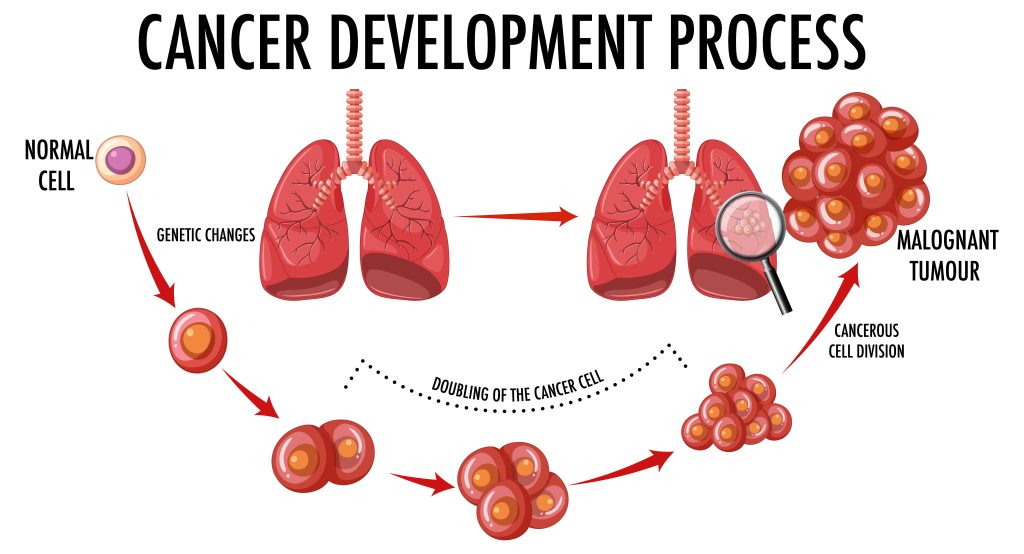

Thoracic cancer is a group of cancers that develop in the thoracic cavity, which includes the lungs, esophagus, and thymus gland.

Common types of thoracic cancer include:

- Lung cancer

- Esophageal cancer

- Thymic cancer

Each type may have different symptoms, risk factors, and treatment options.

Lung cancer is one of the most common types of thoracic cancer and begins in the lungs.